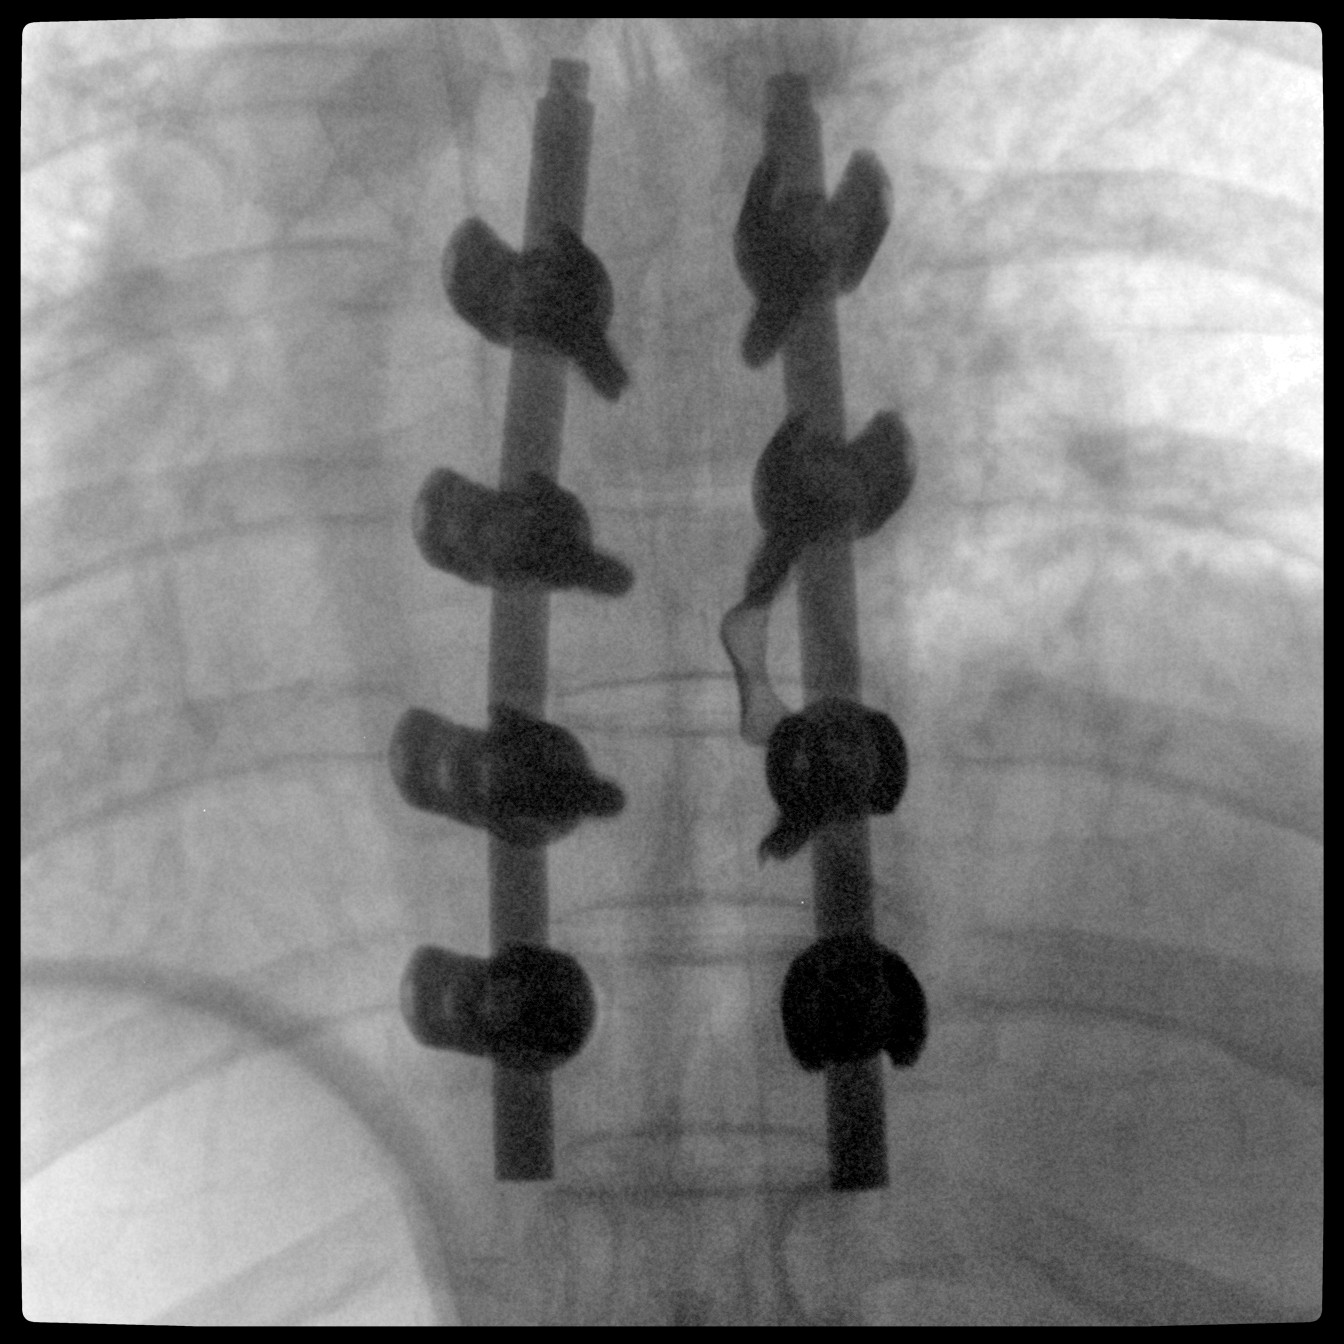

PLX118F-Plus配备了两种平板尺寸,大尺寸动态平板探测器成像面积较传统平板探测器提升了25%以上,在视野需求大的手术中,便于医生更好定位病灶点,规划手术方案,减少因视野范围不足而多次透视、点片造成的不便,不仅提高了手术效率,也减少了辐射剂量。